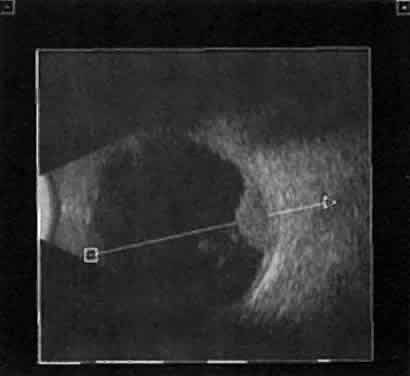

Recent improvements in computer technology and digital B-scan devices have

permitted the development of tomographic (3D) static displays. The

new devices, often called 3D ultrasound instruments, increase understanding

of complex topographic information (Fig. 18). Sophisticated software permits measurements of captured images (linear, area, and

volume) as well as surface renderings18,19 (Figs. 19 and 20). Kinetic (real-time) information is not yet available in 3D and continues